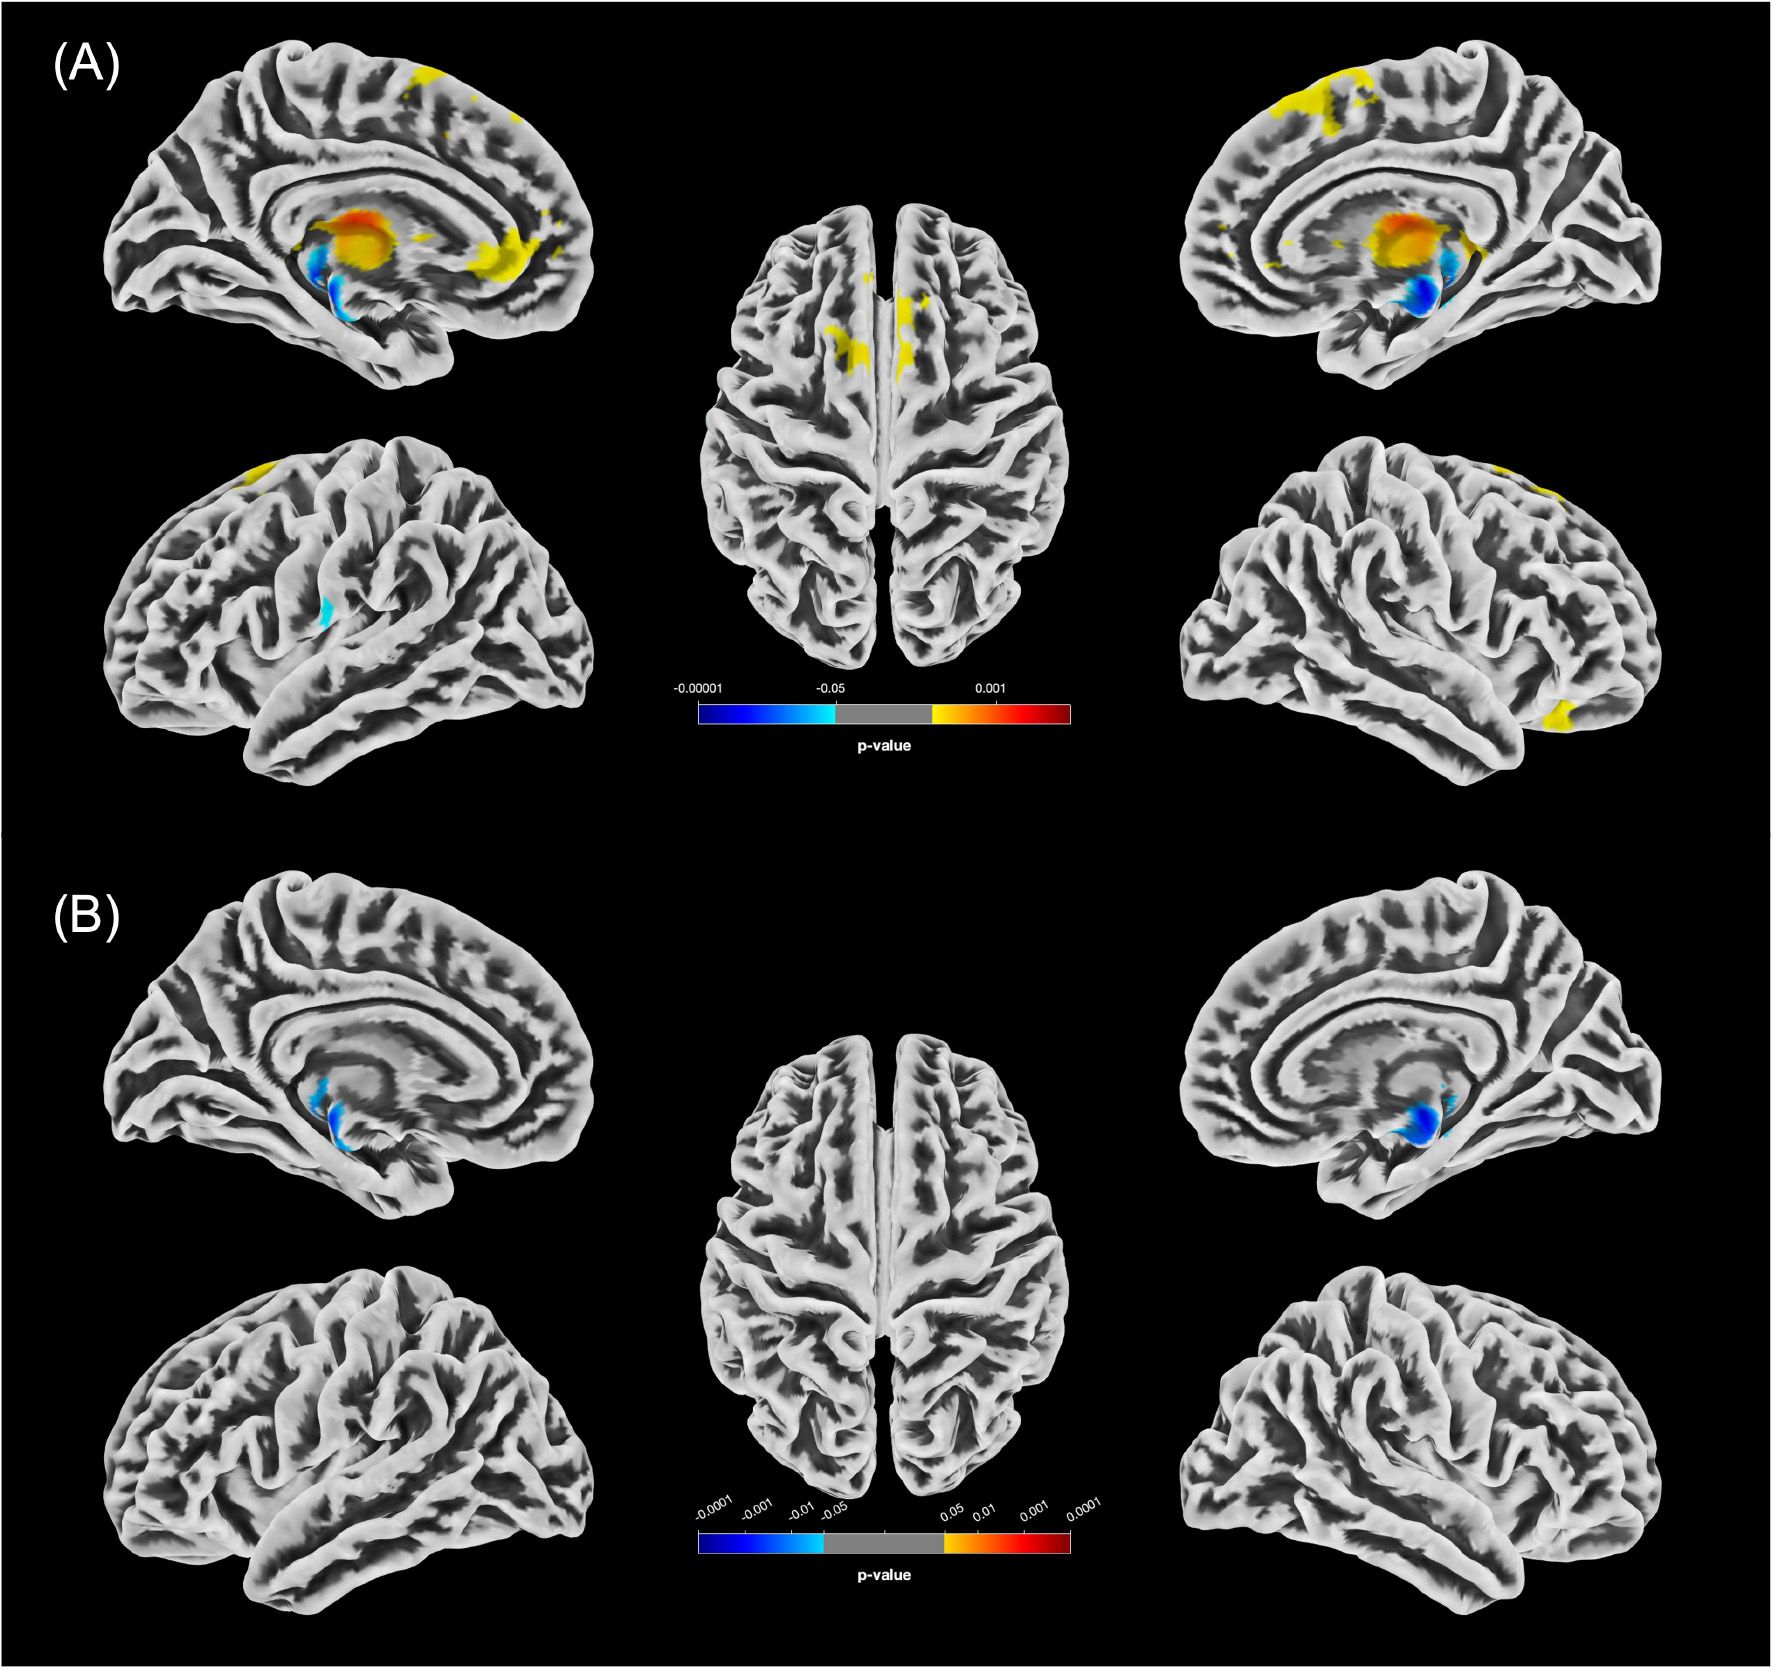

An overview of all significant clusters (kE>100) is provided in Table 5, with their spatial distribution illustrated in Figure 1 (women) and Figure 2 (men).

Figure 1. Statistically significant GMV differences between the female groups (p<0.05, FWE-corrected). (A) Increases in GMV in f-PCn relative to f-HC (f-HC<f-PCn) are shown in yellow/red; decreases (f-HC>f-PCn) in blue. (B) Significant clusters of reduced GMV in f-PCcog compared to f-HC are displayed in blue.

4.2.1 GMV alterations observed in female participants

The distribution of clusters with altered GMV in female participants compared to males in our analysis was more restricted, predominantly involving anterior frontal areas as well as limbic and diencephalic regions, including the ventral diencephalon, hippocampus and thalamus. No significant differences were found between the f-PCn and f-PCcog groups. Notably, the left thalamus consistently demonstrated GMV alterations across all statistically significant female subgroup comparisons, with both increases and decreases observed. Given its heterogenous structure and its central role in cognitive processes (70), thalamic involvement may be particularly relevant to neuropsychiatric manifestations of long-COVID. Supporting this, VBM in patients with mild cognitive impairment, unrelated to COVID-19, similarly revealed volumetric reductions in the left thalamus, along with alterations in the hippocampus and amygdala (39). This convergence underscores the thalamus as a central node whose vulnerability may extend across different conditions associated with cognitive decline.

GMV alterations specific to female participants were also detected in the anterior cingulate gyrus and medial frontal cortex.